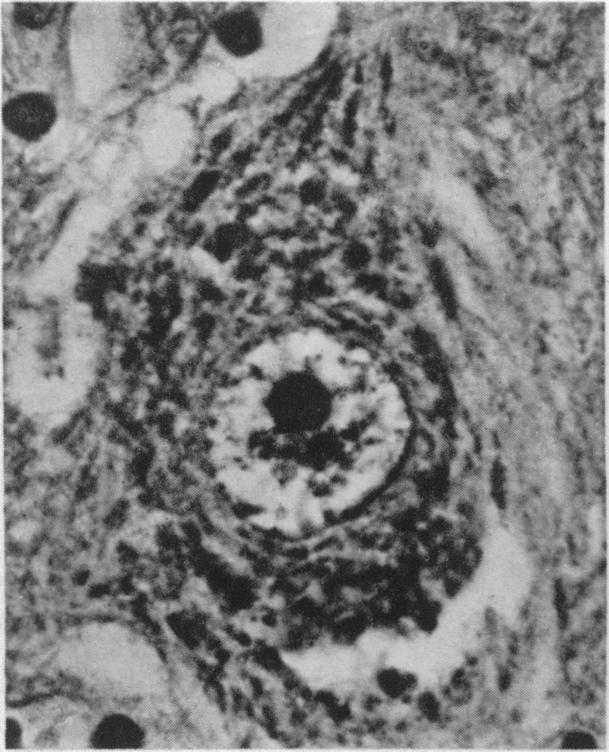

Rheumatoid arthritis in the young.

Br Med J. 1949 Jul 23;2(4620):197-201. doi: 10.1136/bmj.2.4620.197.